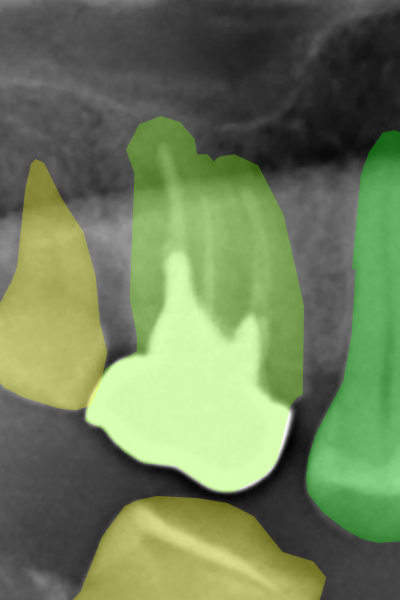

We defined some correction criteria based on our observations during the labeling verification of the first HITL iteration. It was evident that the network predictions were outstanding, yet they were usually worse than manual annotations. This worse performance was mainly due to delicate details that could be polished such as the serrated segmentations originated from the network’s low-resolution masks. Figure 6 shows samples of the serrated patterns on tooth crowns and on lower molars, which were highly frequent, especially on the former. For many applications, such as tooth detection and numbering, these tiny mistakes can be overlooked. However, we decided not to ignore those errors, as we want our data set to be general-purpose. In sum, the labels after correction should be as similar as possible to the manual labels. This determination slowed down the verification procedure significantly because our annotators had to make many tiny adjustments. With this main criterion defined, we proceeded with the other three iterations, reaching in the end 3,150 HITL labeled radiographs.

Refer to caption

(a) Serrated masks on tooth crowns.

(b) Serrated masks on lower molars.

Figure 6: Samples of the serrated pattern due to the network’s low-resolution mask predictions. This pattern frequently occurred on (a) tooth crowns and (b) lower molars, especially the former. The red arrows point to some spots with those patterns.